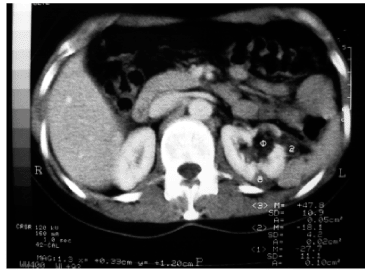

????【四只腎】哈爾濱一家出租汽車公司的張云兵一直自覺精力充沛,干活不累,并未感到與常人有什么不同。后來,他因“腰痛”在哈爾濱市一醫(yī)院泌尿科檢查會診,醫(yī)生發(fā)現(xiàn)他長有4個腎、4條輸尿管。左腎里有一結(jié)石正是導(dǎo)致這次腎絞痛的原因。